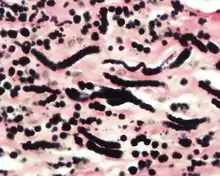

By microscopie view, there is an admixture of heavy dense bands of collagenous tissue dissected by fat and abnormal elastic fibers. The elastic fibers are often quite large and are easily identified. The elastic fibers are coarse, thick, and darkly eosinophilic, often fragmented into globules, creating a "string of pearls" or "pipe cleaner" appearance. Because of degeneration, the elastic fibers will appear as globules with a serrated or "prickled" edge.[4]

The elastic fibers will be highlighted by a Weigert or von Gieson elastic stains.[8]